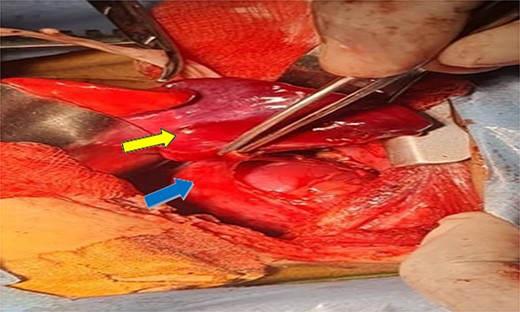

Shows dissection of the sequestration (yellow arrow) and ectopic kidney after separation from fascia of gerota (can see the renal capsule) (blue arrow).